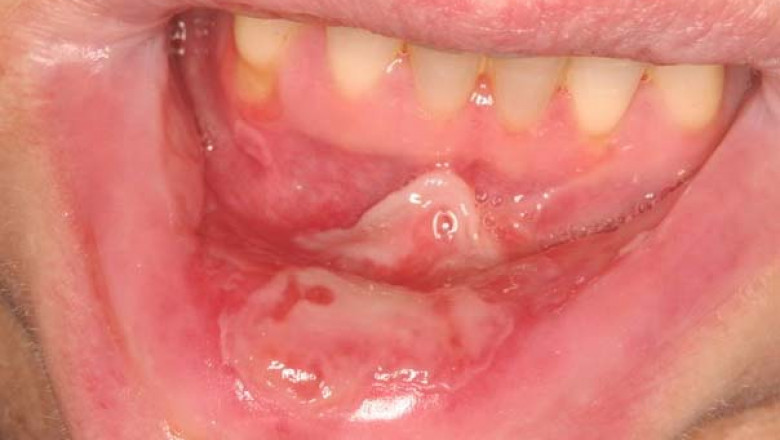

Mucositis is an acute event that mostly self-resolves as the anticancer treatment ends. High dose chemo and radiotherapy to the head and neck region (for example, to treat head and neck cancer and lymphoma) are the major risk factors for the development of oral mucositis. Thus, with the increasing prevalence of head and neck cancer, the incidence of Severe Oral Mucositis is also increasing, especially in the U.S. According to the American Society of Clinical Oncology, in 2021, around 66,630 individuals (48,740 men and 17,890 women) in the U.S. are expected to develop head and neck cancer.

U.S. Severe Oral Mucositis impairs the patient's quality of life and also can be life-threatening because severe infections and delayed or incomplete anticancer treatments may result. One may not stop mucositis from occurring, but few steps can be followed before beginning cancer treatment to help alleviate its side effects and symptoms.